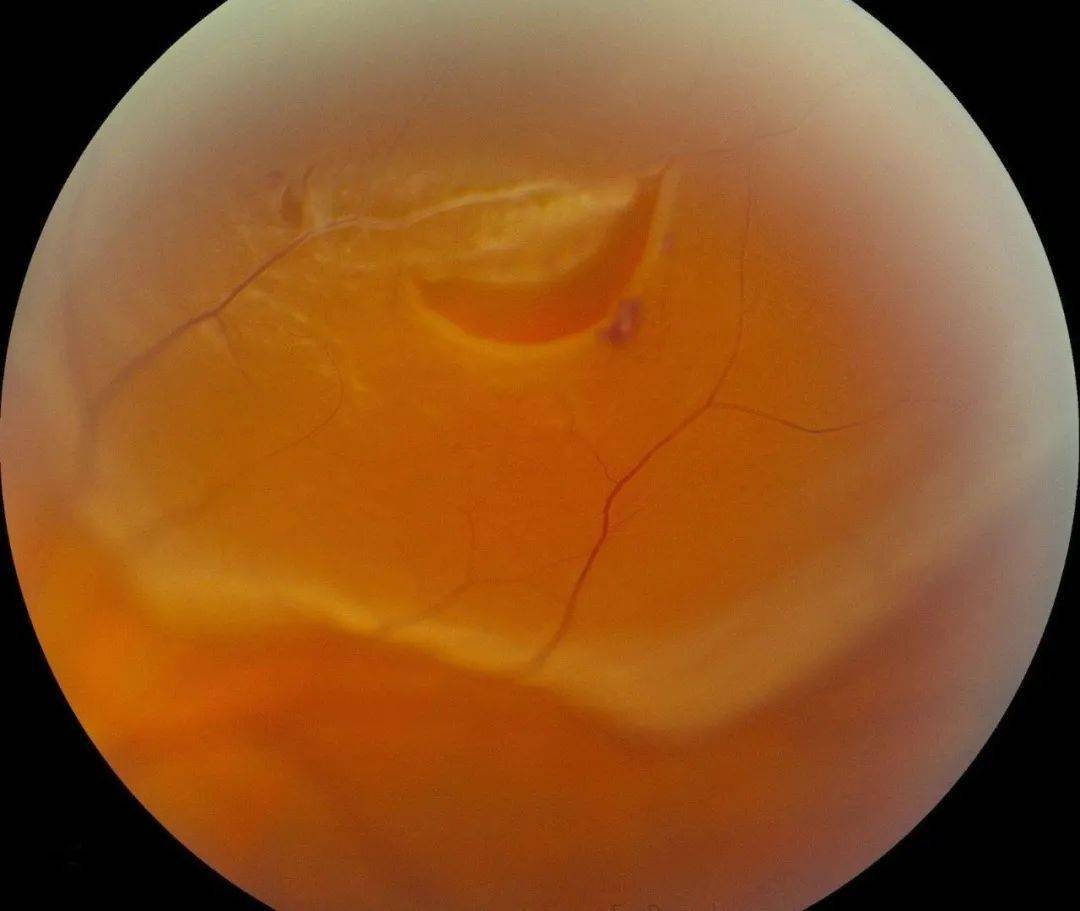

90d前置镜看到的眼底图

视网膜色素变性90d前置镜下所见猪眼球眼底所见波波裂隙灯拍照所用